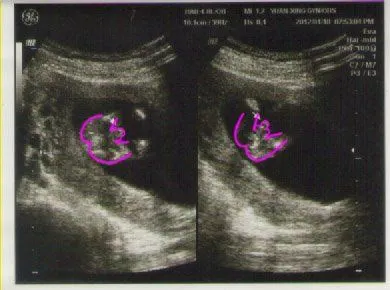

「小柳丁」是阿奇的第二個小孩的代號

說真的,這一胎的報到讓我一整個撼住,久久不能回神

小柳丁的到來雖然開心遠大於緊張害怕;這麼可愛的蘋果總算有個伴來一起長大